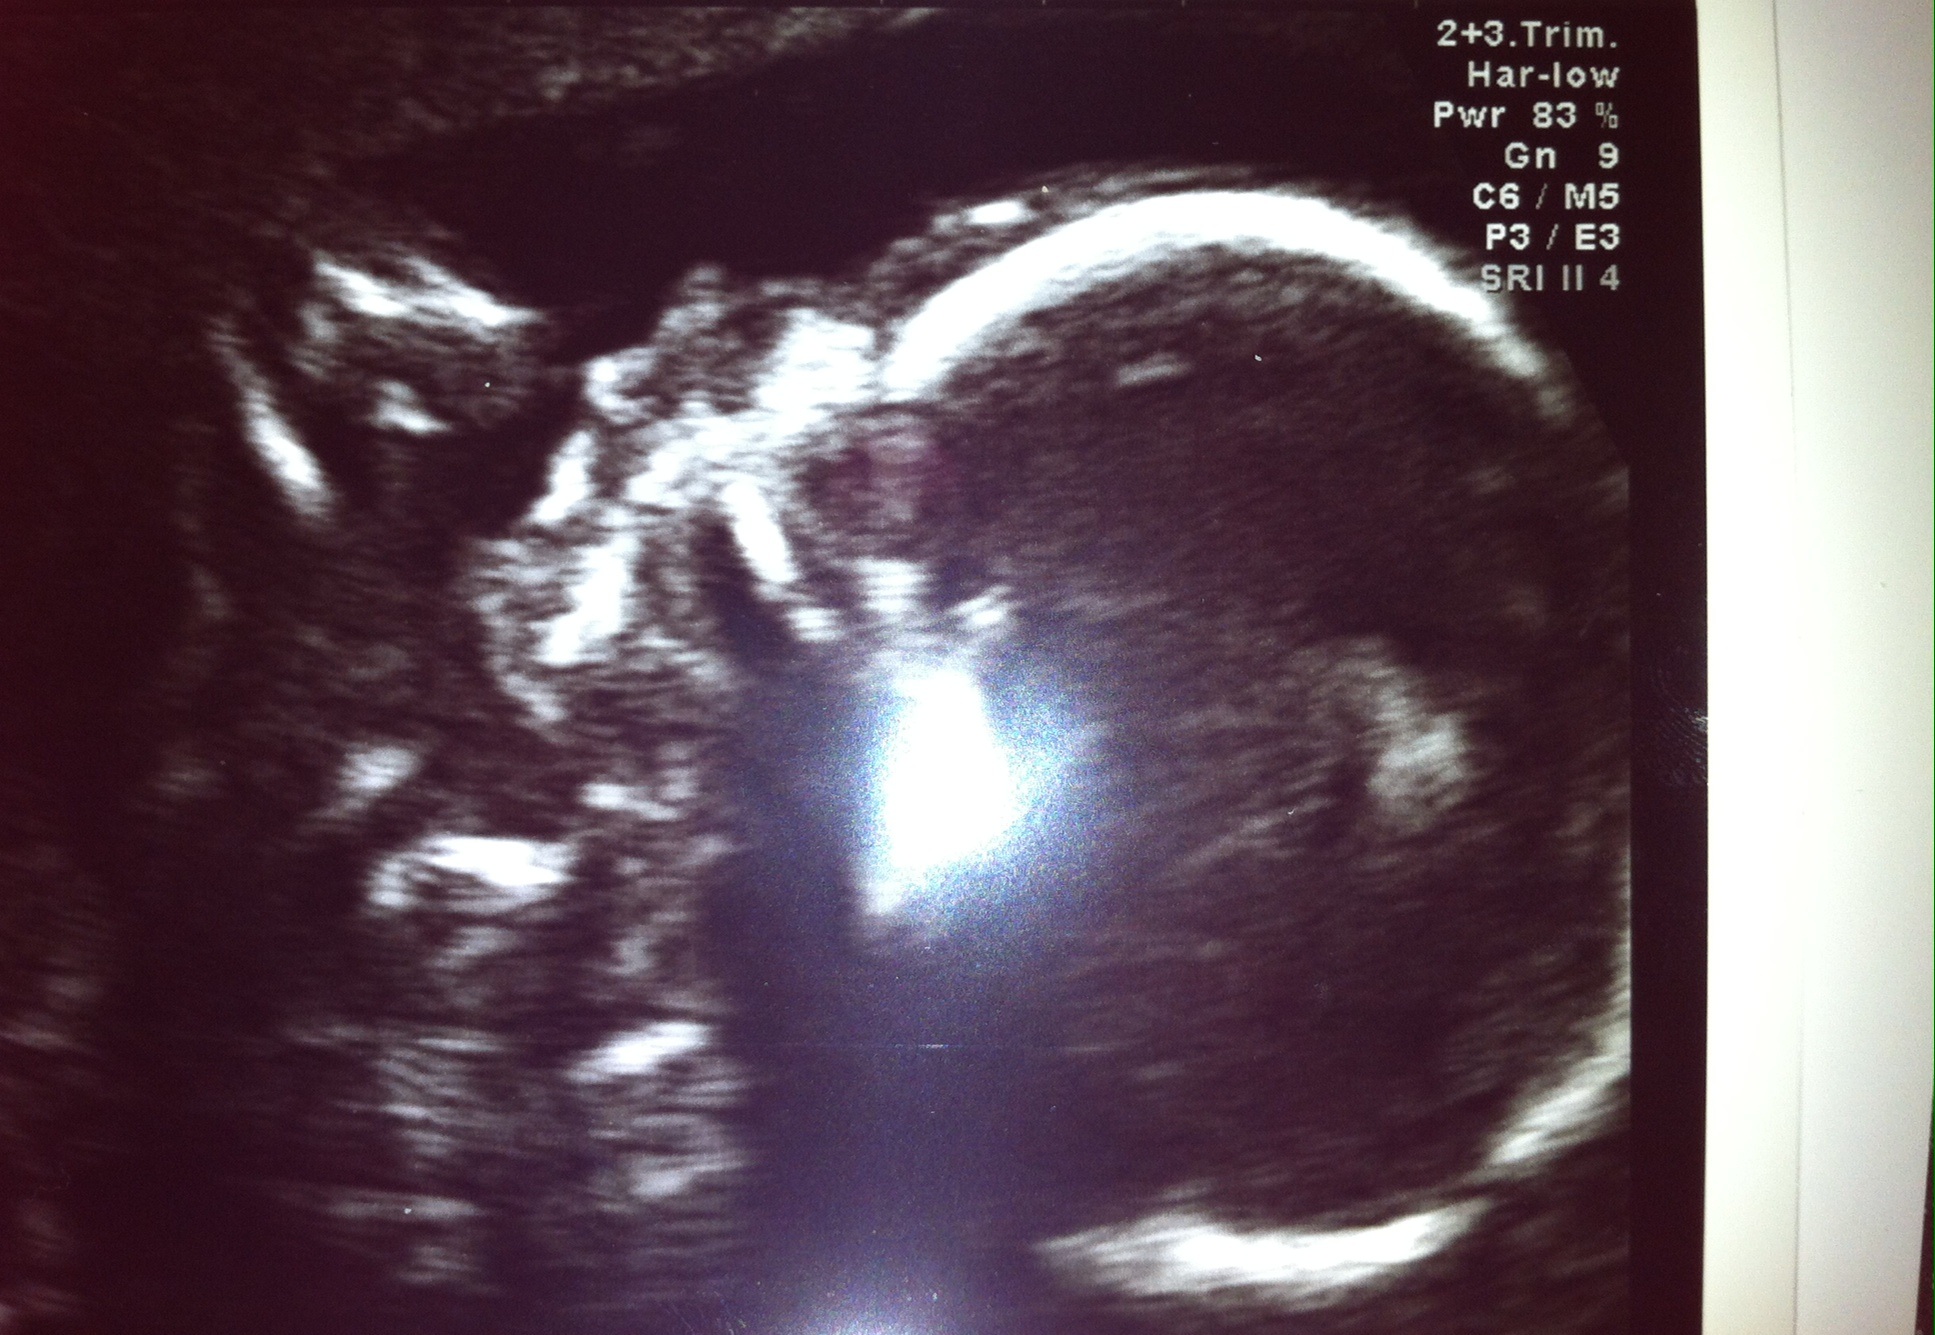

Well here he is my beautiful 3rd baby boy. Decided to get a 3rd scan at a different place , they were brilliant. XxAttachment 19642Attachment 19643

Congratulations on your beautiful baby boy :) what a cute nose!! Xx